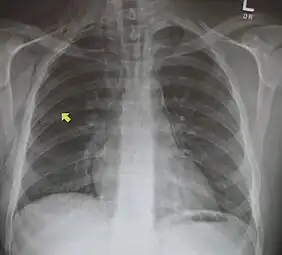

Pneumomediastinum with angel wing sign[14] -